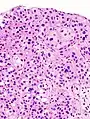

The 1973 WHO grading system for transitional cell carcinomas (papilloma, G1, G2 or G3) is most commonly used despite being superseded by the 2004 WHO[14] grading for papillary types (papillary neoplasm of low malignant potential [PNLMP], low grade, and high grade papillary carcinoma). High-grade carcinoma typically displays more pleomorphism, multiple mitoses, euchromatin and relatively prominent nucleoli, and uneven distribution of nuclei.

Histopathology of urothelial carcinoma of the urinary bladder.

Micrograph of urethral urothelial cell carcinoma. H&E stain